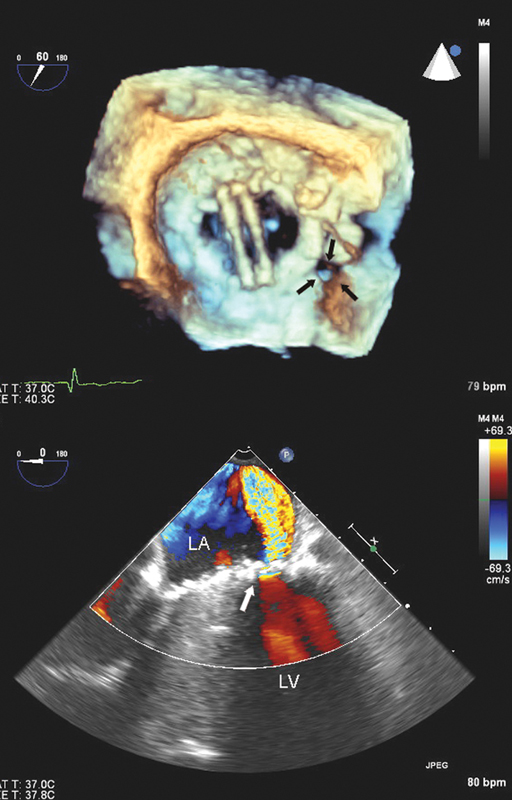

فحوصات تشخيصية لبعض امراض القلب والشرايين التاجية